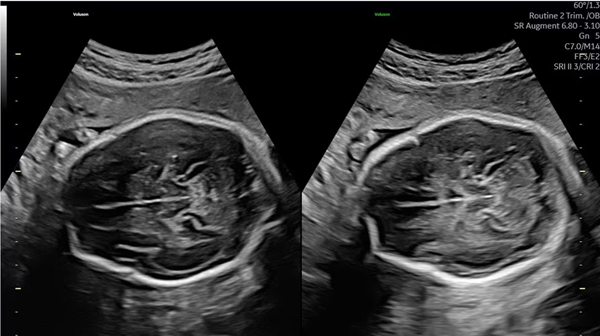

減衰を補うAugmentと、音響陰影を補うShadow Reductionを使用した画像(off/on)